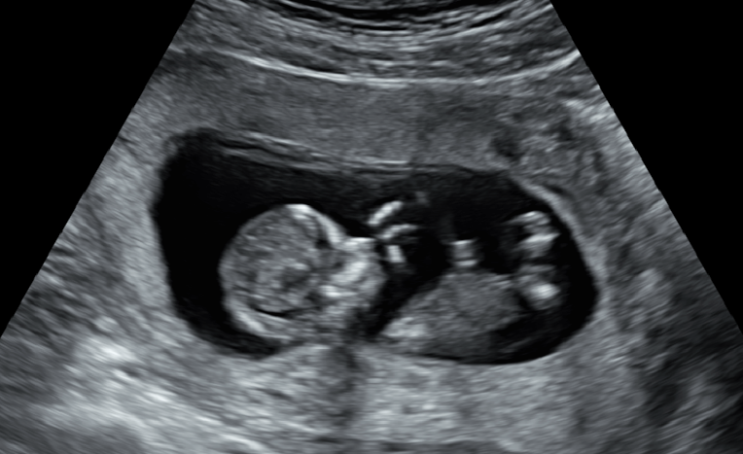

2018년에 미래연에 오셔서 인연을 맺었던 우즈베키스탄 국적의 환자분이십니다. 만 40세의 나이로 내원전 ...

타원에서 신선배아이식 3회와 동결배아이식 2회를 받으셨으나 결과가 좋지 않아 올해 4월에 미래연에 처음 ...